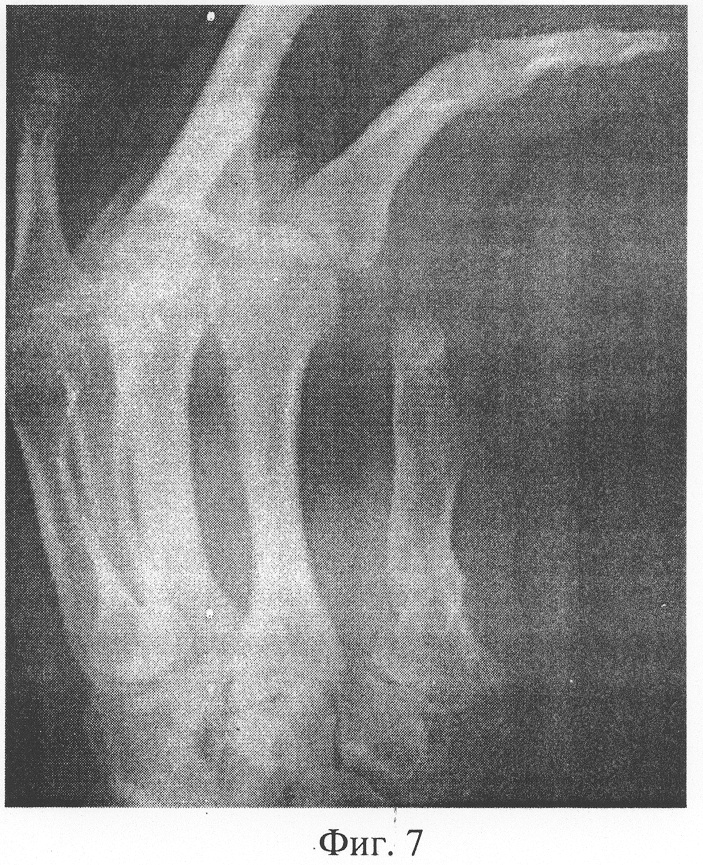

После полного срастания трансплантата с культей 1 пястной кости пациент госпитализирован повторно 28.11.03. ИБ №5679 с диагнозом: Состояние после 1 этапа кожно-костной реконструкции 1 луча левой кисти (Фиг.7, 8).